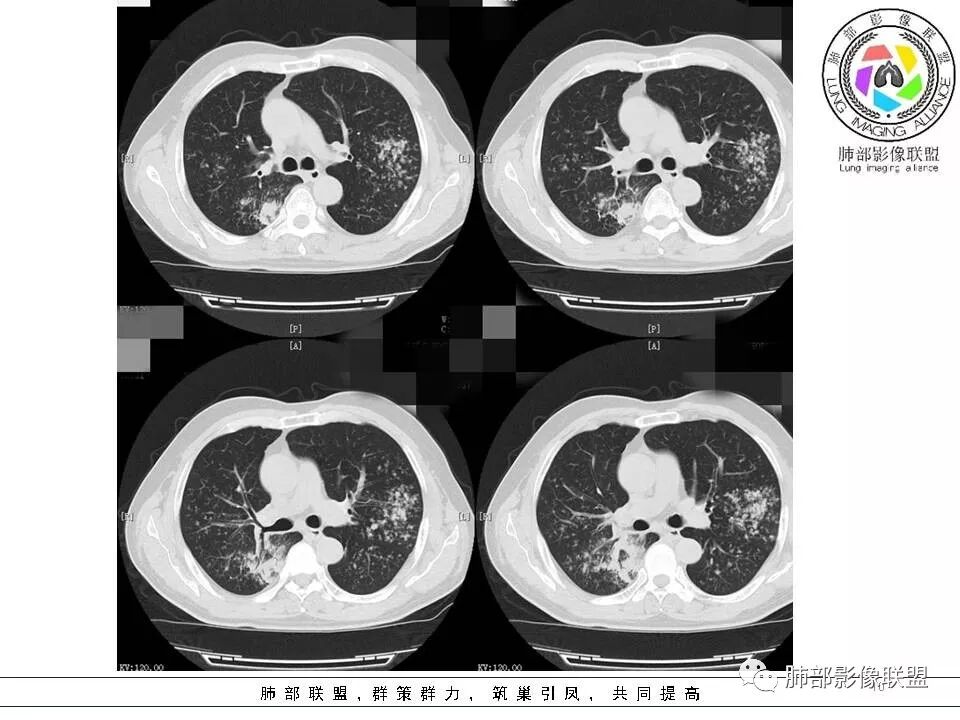

我们分析这2个病例的共同点:双肺都是以外周胸膜下分布为主,均表现为肺大片、斑片实变的肺炎性型改变,而且都有含气支气管的堵塞,这种残“支”败“叶”的异病同影的病例,那我们如何从影像上抽丝剥茧并结合临床分析病例呢?那我们现在按南边老师分析套路,从病变形态与分布、边缘的收缩性、病灶的走形方向、病灶的支气管变化、病灶内坏死及周围情况逐一分析;

病例一

病灶的形态与分布如何?

多发实变影,呈叶段分布,形态及密度都比较单一,比较柔和

病灶的走形如何?                                                                                                以外围胸膜下分布为主,长轴与胸膜平行

病灶的边缘如何:

大部分边缘膨隆,局部边缘稍收缩

病灶内的支气管如何:                                                                            支气管走形通畅自然,部分于近端堵塞,管壁光整

病灶内的坏死如何?:                                                                                             病灶内有坏死空洞,大部分空洞内壁光整,部分空洞内少许分隔影,呈“鬼脸”样空洞

周围情况如何?:                                                                                                   周围肺野有模糊晕,未见明显树芽征,与胸膜有糊墙改变

患者临床轻影像重,CRP增高,社区获得性肺炎常规不考虑,年轻人,不是许多机会性感染的易感人群,特殊性感染性病变有结核和隐球,但是结核形态多发,好发于上叶及下叶背段,密度不均一,通常有树芽,而且结核空洞呈虫蚀样且内壁光整,不作为首先考虑病灶形态单一,有晕征,有空洞及空洞内分隔,病灶分布与胸膜平行,隐球比较符合,但是结核影像多样化,年轻人,也需要临床进一步检查除外结核。    病例为什么不首先考虑OP或淋巴瘤,病灶内支气管情况有助于判别,OP收缩性往往很强,所以病灶内支气管应该稍扩张而且没有堵塞,淋巴瘤起源于支气管粘膜下和肺间质,往往沿血管支气管束方向分布,与胸膜垂直为主,病灶内支气管壁增厚并直达远段,易合并支气管扩张;年轻人肺炎型肺癌少见,而且影像表现也不支持,如果患者治疗效果不好,需要临床进一步检查排查肺癌。